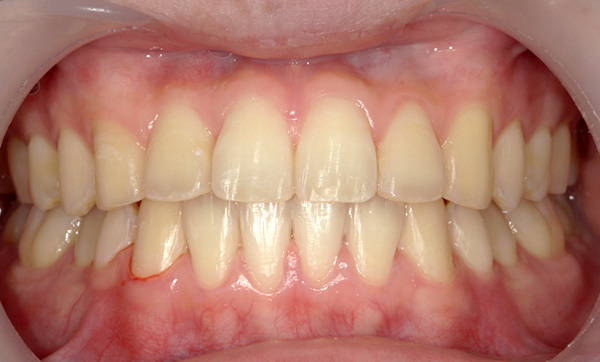

症例_009 「上下の前歯」症例

治療期間:7ヶ月金額:54万円+税20代女性捻転歯一部の反対咬合前歯のガタガタ